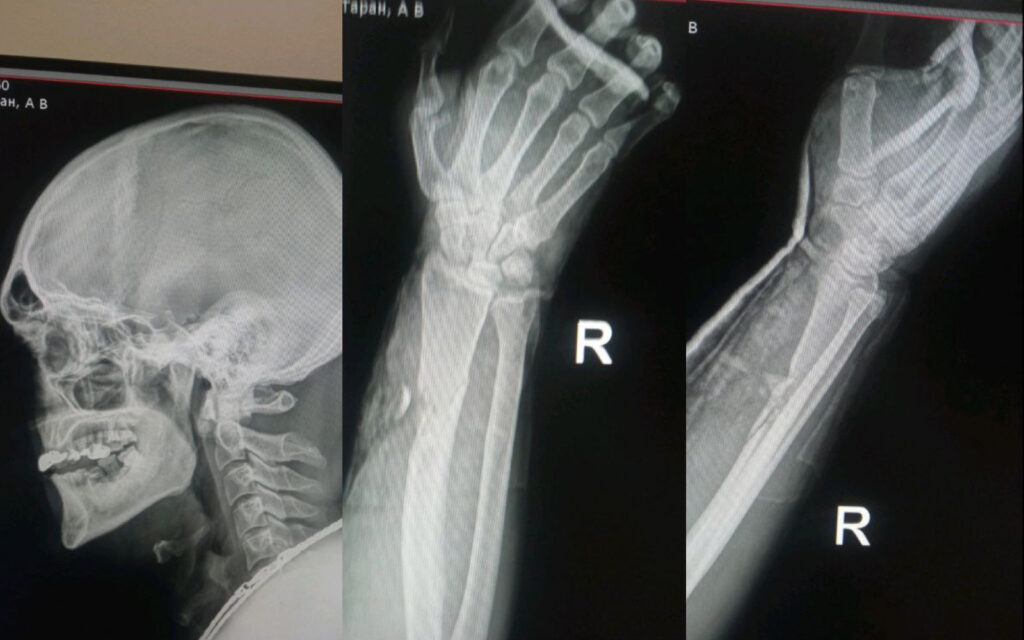

Фото від рідних воїна

27 серпня воїн Андрій Таран відбивав ворожий наступ під Кураховим. У бою захисник дістав вогнепальне поранення та численні травми.

Андрій Таран – воїн 116-ї окремої бригади тероборони. 27 серпня захисник брав участь у відбитті наступу ворога поблизу Курахового, що на Донеччині. У бою захисник дістав вогнепальне уламкове поранення променевої кістки. Пізніше в Андрія Тарана діагностували черепно-мозкову травму, струс мозку та контузію.